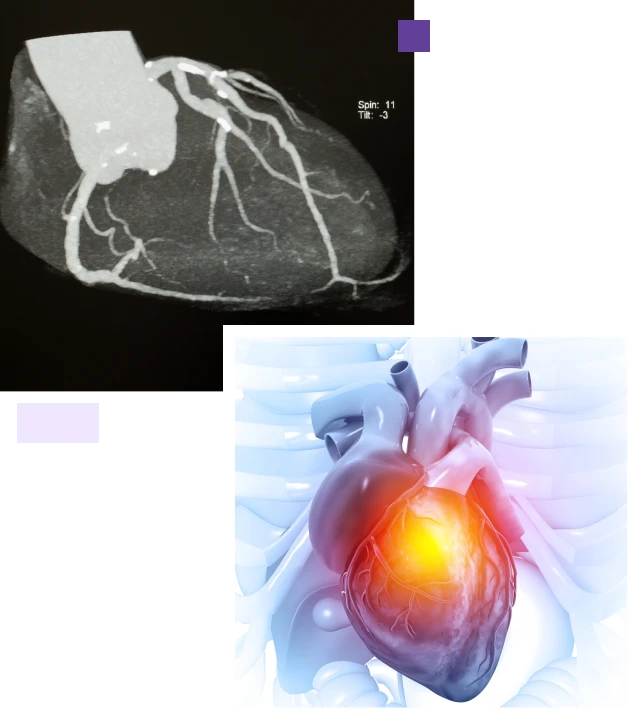

An angiogram is an X-ray procedure that can be prescribed for both diagnostic and remedial purposes of coronary diseases. This is usually the best way to assess for blockages in the blood vessels. An angiogram can detect the narrowing and blockage in your coronary arteries. It would require a dye to be infused into your body, after which X-rays are used to look for blockages. The blockage is assessed and a further treatment plan is prepared by your doctor.

The blood vessels as seen on X-ray. A CT angiography is a procedure that employs CT technology to create images of blood arteries.

Special dye fluids are passed through the catheter to have a clear view of the arteries

X-ray images are clicked as the fluid is passed through the catheter

These X-rays obtained can help understand the abnormalities in the heart